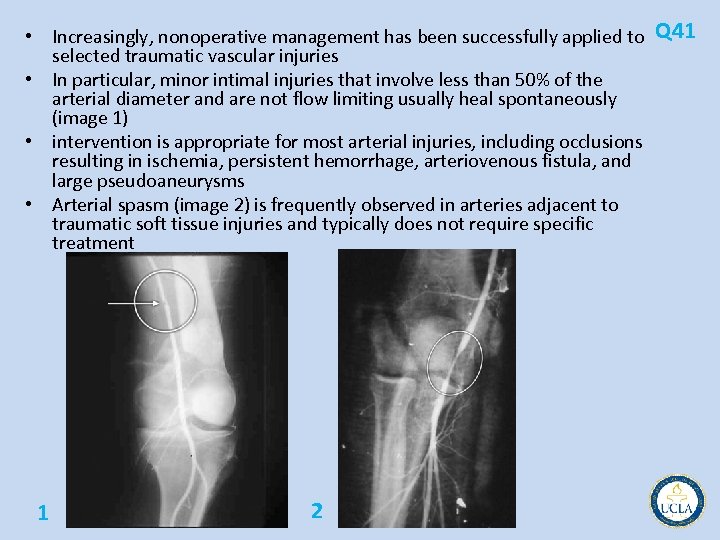

• Increasingly, nonoperative management has been successfully applied to Q 41 selected traumatic vascular injuries • In particular, minor intimal injuries that involve less than 50% of the arterial diameter and are not flow limiting usually heal spontaneously (image 1) • intervention is appropriate for most arterial injuries, including occlusions resulting in ischemia, persistent hemorrhage, arteriovenous fistula, and large pseudoaneurysms • Arterial spasm (image 2) is frequently observed in arteries adjacent to traumatic soft tissue injuries and typically does not require specific treatment 1 2

• • • Most traumatic arteriovenous fistulas (image 3) should be treated either by coil Q 41 embolization or surgical ligation because of their tendency to enlarge with time Arterial occlusion (image 4) usually warrants surgical intervention unless the patient's overall condition precludes surgical intervention or redundant circulation to the affected part is believed to be sufficient to eliminate ischemia Extravasation of contrast (image 5) during angiography indicates ongoing hemorrhage requiring definitive treatment, either in the form of catheter based intervention or surgical repair While small (< 2 cm) posttraumatic, eg, after cardiac catheterization, pseudoaneurysms can be safely observed in anticipation of spontaneous thrombosis, larger pseudoaneurysms require treatment ultrasound guided compression, percutaneous thrombin injection, and conventional surgical repair. 3 4 5